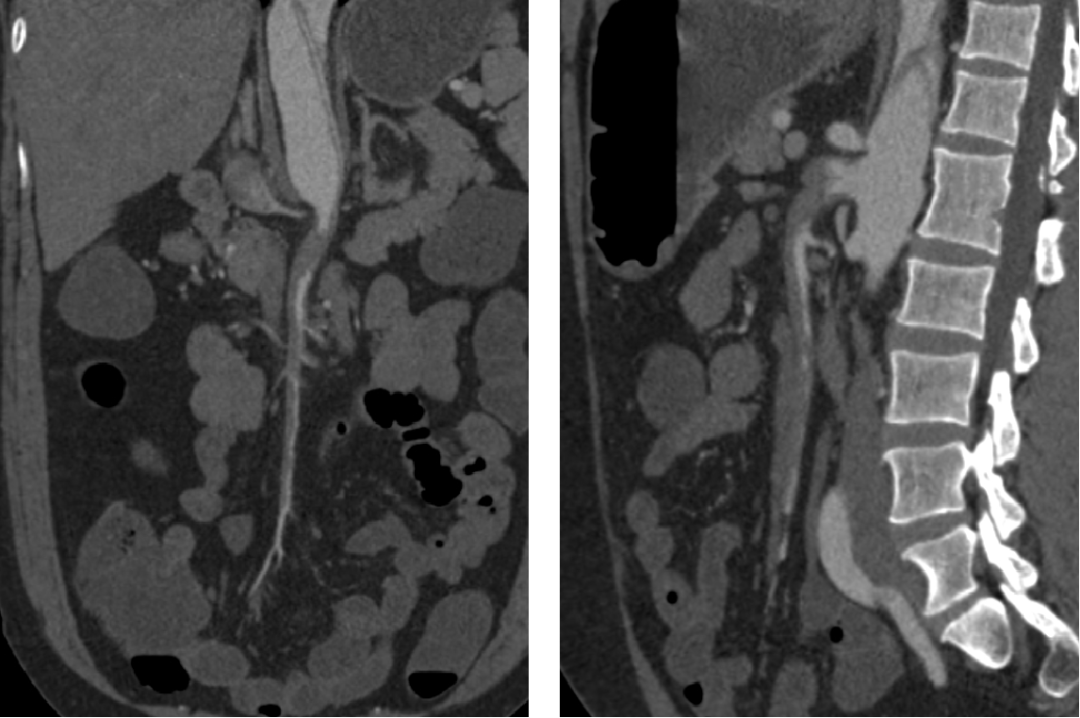

通过下面4个具体病例进一步说明TEVAR在治疗复杂型B型主动脉夹层中的治疗原则、注意事项及应用。

★病例4

急性复杂性AD

STABLE II研究:涉及法国、澳大利亚和美国的3个中心,73例复杂性AD患者使用Zenith TX2 Dissection Endovascular Graft with Pro-Form进行治疗。